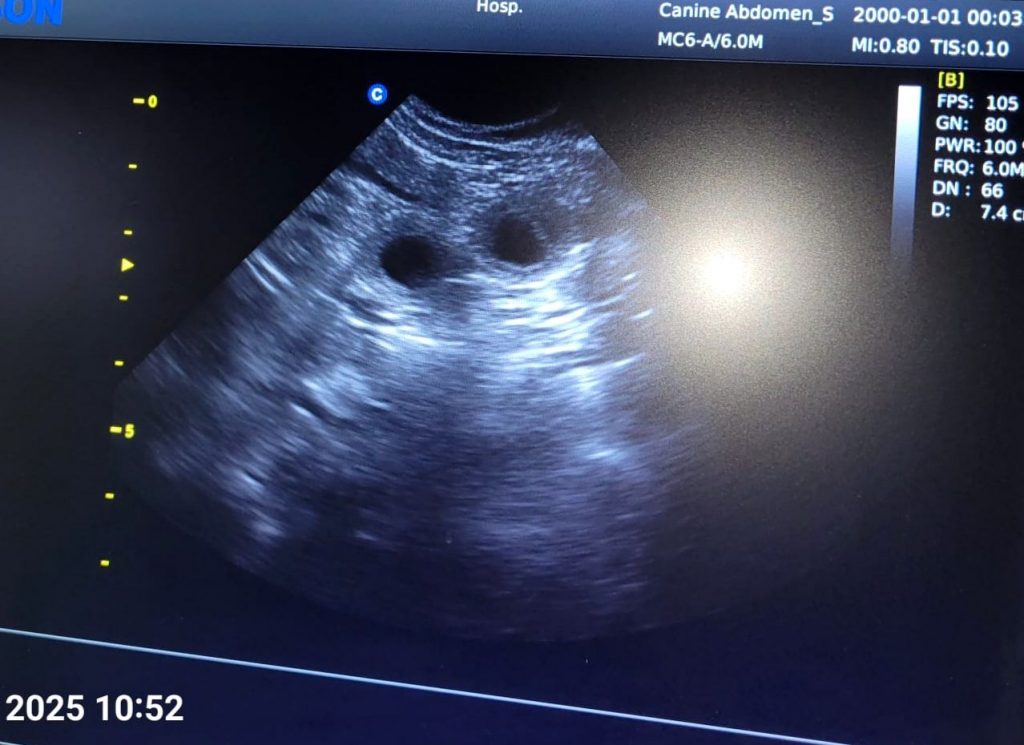

Am 22. Tag sind die Embryonen sichtbar. Der Herzschlag kann zur Diagnose der Trächtigkeit herangezogen werden. Anstrengende Aktivitäten sind jetzt zu vermeiden. Der Ultraschall hat die Trächtigkeit bestätigt.

Dies ist der beste Zeitpunkt, um die Trächtigkeit anhand des Herzschlags zu diagnostizieren. Die Embryonen sind etwas walnussgroß und sind gleichmäßig im Uterus verteilt.

In etwa 3–4 Wochen werden wir mit Liselotte zum Ultraschall zu unserer Tierärztin fahren. Sehr gerne können wir uns im Anschluss persönlich kennenlernen. Bei Interesse sind wir natürlich schon jetzt telefonisch für Sie erreichbar.